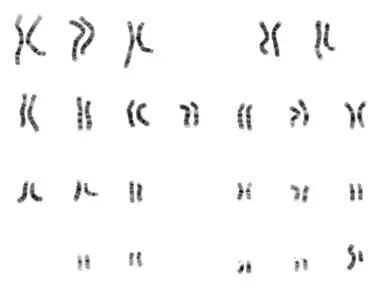

Following the advent of procedures that allowed easy enumeration of chromosomes, discoveries were quickly made related to aberrant chromosomes or chromosome number.

Constitutional cytogenetics: In some congenital disorders, such as Down syndrome, cytogenetics revealed the nature of the chromosomal defect: a "simple" trisomy. Abnormalities arising from nondisjunction events can cause cells with aneuploidy (additions or deletions of entire chromosomes) in one of the parents or in the fetus. In 1959, Lejeune[20] discovered patients with Down syndrome had an extra copy of chromosome 21. Down syndrome is also referred to as trisomy 21.

Other numerical abnormalities discovered include sex chromosome abnormalities. A female with only one X chromosome has Turner syndrome, whereas a male with an additional X chromosome, resulting in 47 total chromosomes, has Klinefelter syndrome. Many other sex chromosome combinations are compatible with live birth including XXX, XYY, and XXXX. The ability for mammals to tolerate aneuploidies in the sex chromosomes arises from the ability to inactivate them, which is required in normal females to compensate for having two copies of the chromosome. Not all genes on the X chromosome are inactivated, which is why there is a phenotypic effect seen in individuals with extra X chromosomes.

Trisomy 13 was associated with Patau syndrome and trisomy 18 with Edwards syndrome.

Acquired cytogenetics: In 1960, Peter Nowell and David Hungerford[21] discovered a small chromosome in the white blood cells of patients with Chronic myelogenous leukemia (CML). This abnormal chromosome was dubbed the Philadelphia chromosome - as both scientists were doing their research in Philadelphia, Pennsylvania. Thirteen years later, with the development of more advanced techniques, the abnormal chromosome was shown by Janet Rowley to be the result of a translocation of chromosomes 9 and 22. Identification of the Philadelphia chromosome by cytogenetics is diagnostic for CML. More than 780 leukemias and hundreds of solid tumors (lung, prostate, kidney, etc.) are now characterized by an acquired chromosomal abnormality, whose prognostic value is crucial. The identification of these chromosomal abnormalities has led to the discovery of a very large number of "cancer genes" (or oncogenes). The increasing knowledge of these cancer genes now allows the development of targeted therapies, which transforms the prospects of patient survival. Thus, cytogenetics has had and continues to have an essential role in the progress of cancer understanding. Large databases (Atlas of Genetics and Cytogenetics in Oncology and Haematology, COSMIC cancer database, Mitelman Database of Chromosome Aberrations and Gene Fusions in Cancer) allow researchers and clinicians to have the necessary corpus for their work in this field.

In the late 1960s, Torbjörn Caspersson developed a quinacrine fluorescent staining technique (Q-banding) which revealed unique banding patterns for each chromosome pair. This allowed chromosome pairs of otherwise equal size to be differentiated by distinct horizontal banding patterns. Banding patterns are now used to elucidate the breakpoints and constituent chromosomes involved in chromosome translocations. Deletions and inversions within an individual chromosome can also be identified and described more precisely using standardized banding nomenclature. G-banding (utilizing trypsin and Giemsa/ Wright stain) was concurrently developed in the early 1970s and allows visualization of banding patterns using a bright field microscope.

The routine chromosome analysis (Karyotyping) refers to analysis of metaphase chromosomes which have been banded using trypsin followed by Giemsa, Leishmanns, or a mixture of the two. This creates unique banding patterns on the chromosomes. The molecular mechanism and reason for these patterns are unknown, although it likely related to replication timing and chromatin packing.

Several chromosome-banding techniques are used in cytogenetics laboratories. Quinacrine banding (Q-banding) was the first staining method used to produce specific banding patterns. This method requires a fluorescence microscope and is no longer as widely used as Giemsa banding (G-banding). Reverse banding, or R-banding, requires heat treatment and reverses the usual black-and-white pattern that is seen in G-bands and Q-bands. This method is particularly helpful for staining the distal ends of chromosomes. Other staining techniques include C-banding and nucleolar organizing region stains (NOR stains). These latter methods specifically stain certain portions of the chromosome. C-banding stains the constitutive heterochromatin, which usually lies near the centromere, and NOR staining highlights the satellites and stalks of acrocentric chromosomes.

High-resolution banding involves the staining of chromosomes during prophase or early metaphase (prometaphase), before they reach maximal condensation. Because prophase and prometaphase chromosomes are more extended than metaphase chromosomes, the number of bands observable for all chromosomes (bands per haploid set, bph; "band level") increases from about 300 to 450 to as many as 800. This allows the detection of less obvious abnormalities usually not seen with conventional banding.[23]